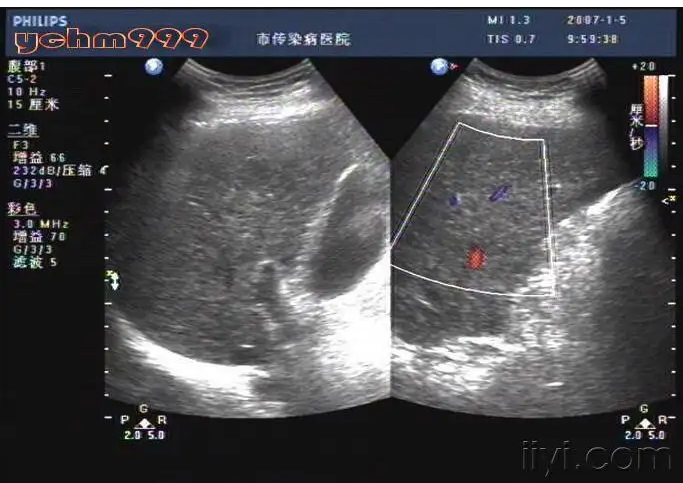

彩色多普勒超声对肝硬化门静脉血流动力学与压力的相关研究

河北省科技成果展示交易中心